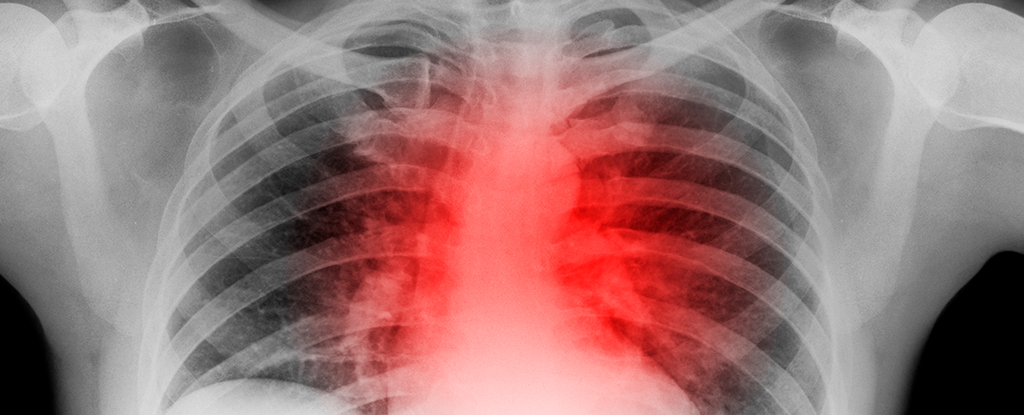

Dve najväčšie smrtiace choroby na svete sú kardiovaskulárne ochorenia a rakovina. Tieto dve choroby napríklad v USA spolu predstavujú takmer 50 % úmrtí. A hoci sa na prvý pohľad zdajú úplne odlišné, novoobjavené paralely medzi ich vznikom a vývojom znamenajú, že niektoré liečebné postupy môžu byť účinné proti obom. Ukázalo sa, že malé, upravené nanočastice, ktoré sa môžu zamerať na špecifické imunitné bunky, môžu byť spôsobom liečby rakoviny aj kardiovaskulárnych ochorení. Ateroskleróza je najsmrteľnejšou formou kardiovaskulárneho ochorenia.

Vzniká v dôsledku zápalu a hromadenia tuku, cholesterolu a iných lipidov v stene ciev, čím sa vytvára plak. Väčšina srdcových infarktov je spôsobená prasknutím plaku. Snaha tela zaceliť ranu môže vytvoriť krvnú zrazeninu, ktorá zablokuje cievy a vyústi do infarktu. Na druhej strane rakovina zvyčajne vzniká v dôsledku genetických mutácií, ktoré spôsobujú nekontrolovateľné delenie buniek. Nekontrolovateľný, rýchly rast buniek, ktorý sa nelieči, môže ...